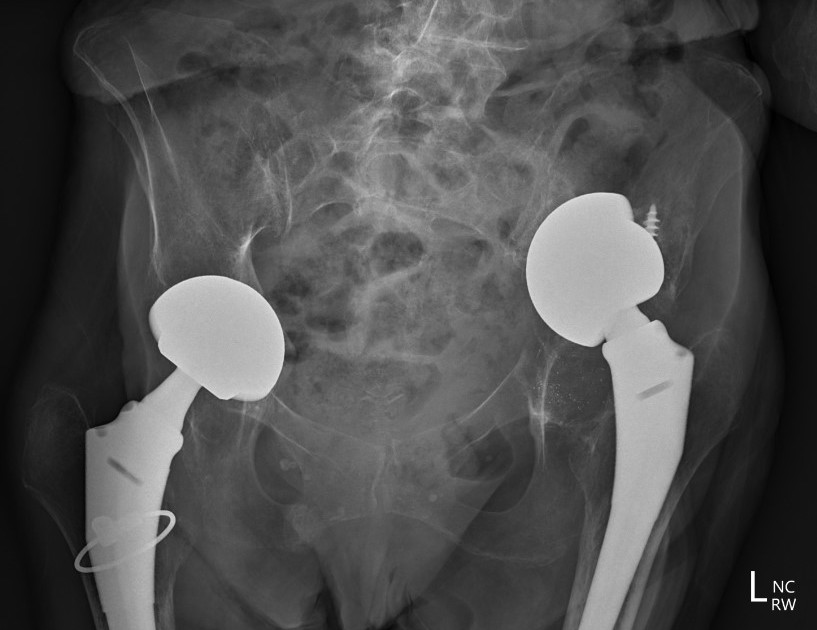

Intra-pelvic cement / components

- danger with removal / revision

- CT angiogram pre-operatively

- may require separate intrapelvic exposure

- alert general surgeons / vascular surgeons